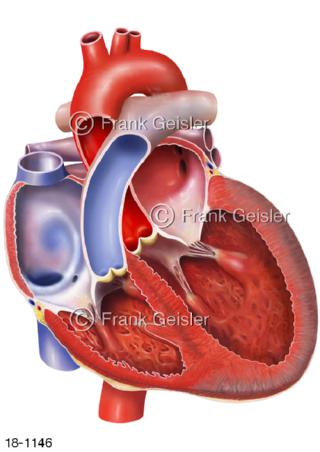

18-1146 Herzinsuffizienz Herzschwäche Herz